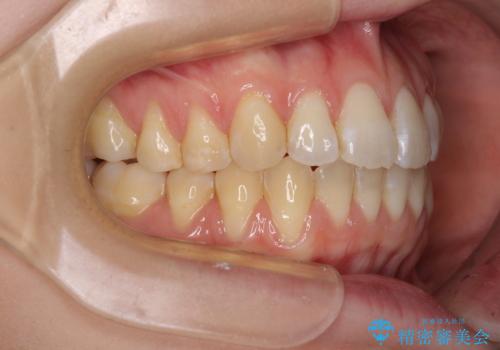

気になるデコボコとオープンバイト インビザラインでの矯正治療

- 前歯のデコボコと上下が開いていることを気にして来院された患者様です。

いわゆるオープンバイトは、インビザラインによる治療が適しているため、インビザラインにて治療を行うこととしました。

オープンバイトは容易に後戻りを起こすため、少しでも後戻りリスクを軽減するために舌癖改善のトレーニングをしっかりと行っていただきました。